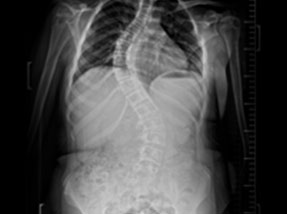

• Post Surgery

Case 1